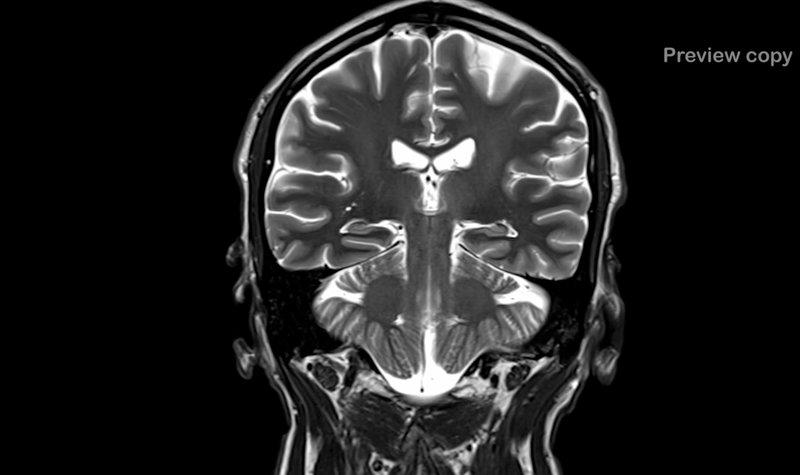

Pål berättar i Sveriges mästerkock att han tidigare blivit brutalt överfallen och misshandlad. Traumat mot huvudet har i sin tur orsakat 12 hjärnblödningar som gett honom ett bestående men i form av helt uteblivet luktsinne.

– Jag har efteråt drabbats av 12 hjärnblödningar och den som gett bestående men är den som sitter där luktsinnet sitter. Det betyder att jag aldrig mer kommer att ha något luktsinne, berättar han.